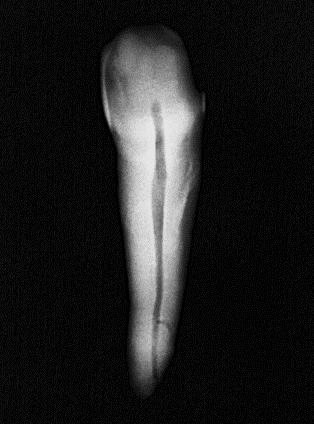

Se utilizaron 46 dientes extraídos unirradiculares superiores e inferiores con caries, pero sin compromiso radicular: sin ápices abiertos Los dientes con reabsorción radicular, fractura apical, caries que comprometieralaraízyápicesabiertosfueron descartados. Cada diente fue sometido a un proceso de limpieza por medio de ultrasonido para la remoción de cálculo y restos de tejido periodontal. Se le asigno un número a cada dienteysetomóunafotografíainicial(Figura 1).

Figura 1

Fotografía inicial de OD#27

Fuente: Pérez V, Salinas L. 2022.